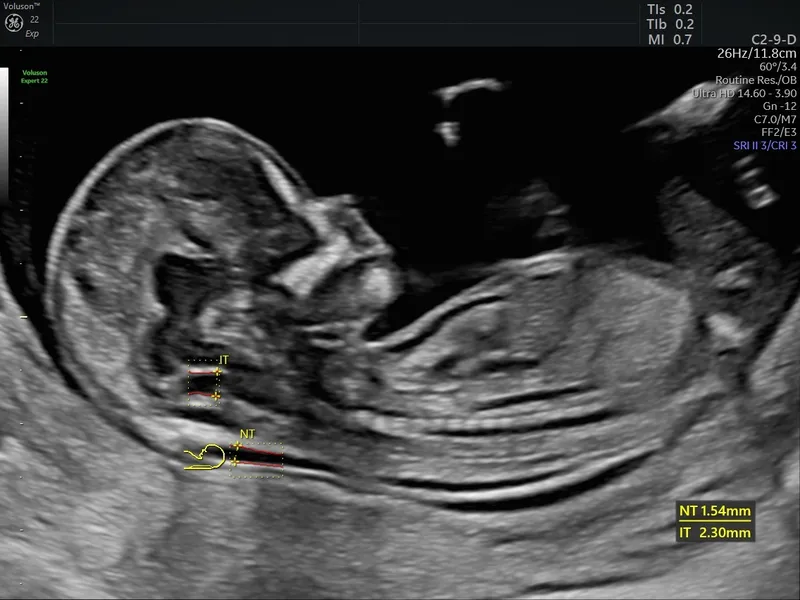

- Combined Test: Serum PAPP-A & β-hCG + Nuchal Translucency (NT) ultrasound.

⭐ Nuchal translucency (NT) is a key marker; an increased NT measurement is associated with a higher risk for aneuploidies like Trisomy 21.